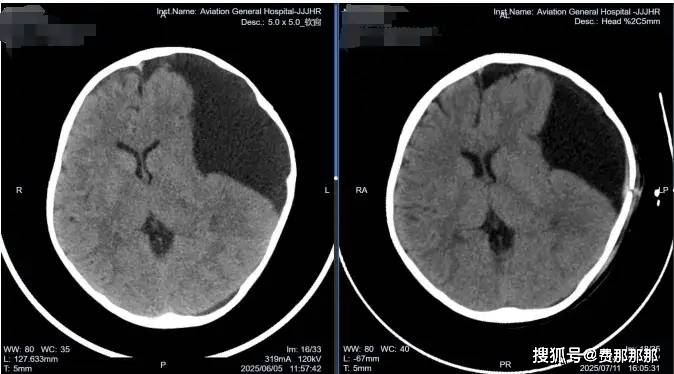

蛛网膜囊肿是儿童常见的先天性颅内病变,传统治疗需开颅手术或依赖分流管植入,但终生带管可能引发感染、梗阻等并发症。近日,北京航空总医院神经外四科肖庆主任团队通过“软性神经内镜技术”,成功为一名4岁复杂蛛